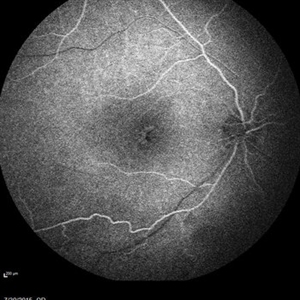

Retinal Dystrophy of 24-Year-Old Male/ Fluorescein Angiogram OD

Fluorescein angiography of a 24-year-old male. Juvenile retinoschisis on OCT. FA shows outer retinal staining. Could be associated with Goldman Farve Syndrome.

Photographer: Zach Dupureur OCT-C

Imaging device: Heidelberg Spectralis

Condition/keywords: Goldmann-Favre Syndrome, juvenile retinoschisis, retinal dystrophy